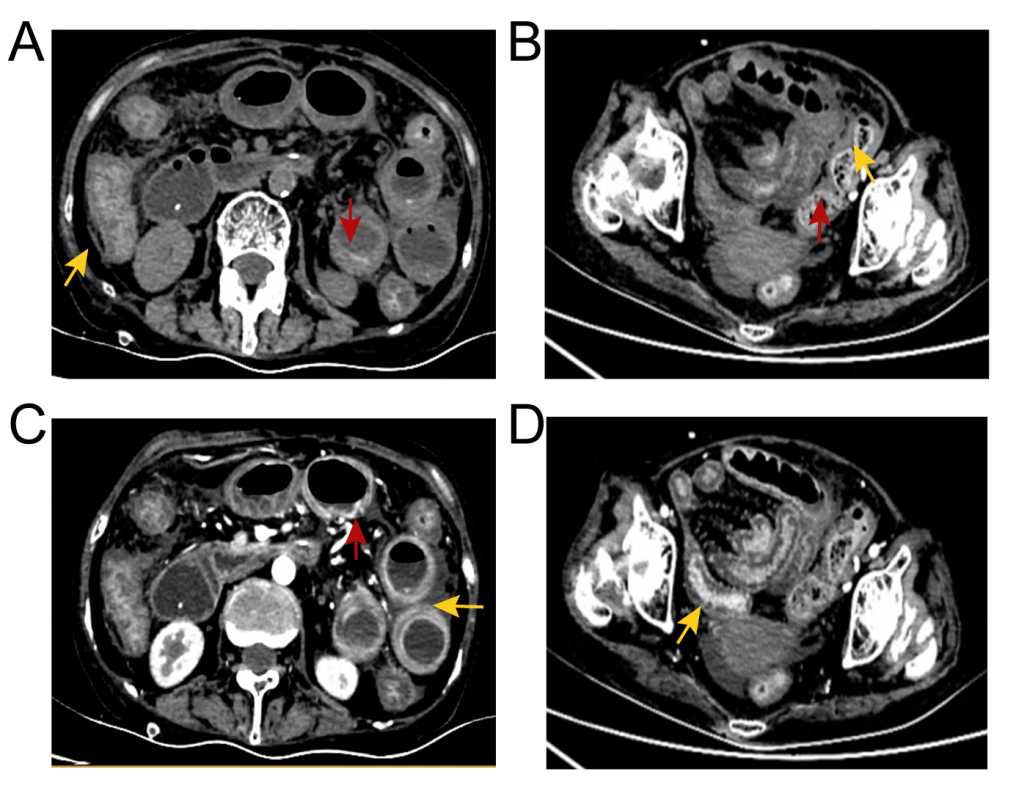

Ò»Ãû63Ë껼ÕßÈëԺǰÓÉÓÚ¼²²¡Ê·ºã¾Ã·þÓÃÃâÒßÒÖÖÆ¼Á¡£¡£¡£¡£¡£¡£ÈëԺʱ£¬£¬£¬£¬£¬»¼ÕßÖ÷ËßʳÓû²»Õñ¡¢¶ñÐÄ¡¢ÍÂÄæ¡¢¸¹Õ͵ÈÖ¢×´ÒÑÒ»Á¬½üÒ»ÖÜ¡£¡£¡£¡£¡£¡£ ¾Ìå¸ñ¼ì²éÏÔʾ£ºË«ÏÂÖ«Ë®Öס¢³¦Ãù΢Èõ¡¢¸¹²¿Ñ¹ÕÍ¡£¡£¡£¡£¡£¡£¼ì²éÀú³ÌÖУ¬£¬£¬£¬£¬»¼ÕßËÄ֫δ¼û¼¡Èâѹʹ£¬£¬£¬£¬£¬¼¡ËἤøˮƽδÓÐÏÔ×ÅÒì³££¬£¬£¬£¬£¬É¨³ý¼¡Ñ׿ÉÄÜ£»£»£»£»£»£»Ë«·ÎºôÎüÒôÇåÎúÇÒÎÞ¸ÉʪÔÓÒô£»£»£»£»£»£»¸ÎÉö¹¦Ð§Ö¸±êÕý³££¬£¬£¬£¬£¬B³¬Ò²ÏÔʾ¸ÎÔà¾ÞϸÐÎ̬Õý³££¬£¬£¬£¬£¬ÃܶÈÔȳƣ»£»£»£»£»£»³¬ÉùÐĶ¯Í¼ÎÞÒì³££¬£¬£¬£¬£¬ÐÄÔàËõ¶ÌºÍÊæÕŹ¦Ð§Õý³££¬£¬£¬£¬£¬¾ùÓë¼ÈÍù±¨µÀA. algeareѬȾµÄÁÙ´²±íÐͲ»·û¡£¡£¡£¡£¡£¡£ »¼Õß½ÓÊÜ¡°³¦¹£×衱µÄÖÎÁƼƻ®£¬£¬£¬£¬£¬ÔÚÖÎÁƽ׶ÎÖи¹ÕͼÓÖØ£¬£¬£¬£¬£¬²¡Çé½øÒ»²½¶ñ»¯¡£¡£¡£¡£¡£¡£ ¸¹²¿ÅÌËã»ú¶Ï²ãɨÃèµÄ´ú±íÐÔͼÏñ¡£¡£¡£¡£¡£¡£»£»£»£»£»£»ÆÉ«¼ýÍ·ÏÔʾ³¦±ÚÔöºñºÍճĤˮÖ×£»£»£»£»£»£»ºìÉ«¼ýÍ·ÏÔʾð¤Ä¤³äѪ£»£»£»£»£»£»³¦±ÚÖÜΧģºýµÄÖ¬·¾¼ä϶Åú×¢¸¹Ç»»ýÒº¡£¡£¡£¡£¡£¡£

¸¹²¿ÅÌËã»ú¶Ï²ãɨÃè(CT)ÏÔʾ¸ÎÔà¡¢µ¨ÄÒ¡¢ÉöÔà¡¢ÒÈÏÙ¡¢×Ó¹¬ºÍ°òë×δ¼ûÒìÑù£¬£¬£¬£¬£¬µ«³¦±ÚÔöºñ£¬£¬£¬£¬£¬³¦±ÚÖÜΧ֬·¾¿Õ¼äÄ£ºý£¬£¬£¬£¬£¬Õ³Ä¤Ë®Ö×£¬£¬£¬£¬£¬¸¹Ç»ÖдæÓдó×Ú¸¹Ë®¡£¡£¡£¡£¡£¡£ÓÚÊÇ£¬£¬£¬£¬£¬ÔÚ³¬ÉùÖ¸µ¼Ï¶Ի¼ÕßÐи¹Ç»´©´ÌºÍ¸¹Ë®ÒýÁ÷¡£¡£¡£¡£¡£¡£¸¹Ë®Ñù±¾µÄ¿¹ËáȾɫ¡¢Î¢ÉúÎï×÷Óý£¨Ï¸¾úºÍÕæ¾ú£©¼°Ï¸°û²¡ÀíѧЧ¹û¾ùΪÒõÐÔ¡£¡£¡£¡£¡£¡£